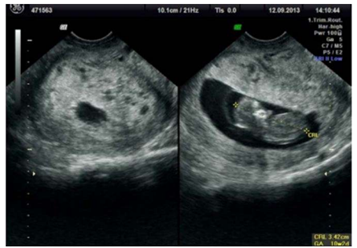

Paciente de 27 anos, G2P1A0, comparece à consulta de

pré-natal com 10 semanas de gestação pela data da

última menstruação, trazendo o exame de

ultrassonografia transvaginal mostrado na imagem.

Relata episódios de sangramento vaginal leve e

intermitente nas últimas duas semanas. Ao exame físico,

apresenta altura uterina maior que o esperado para a

idade gestacional e beta-hCG quantitativo com valores

acima do percentil 95 para a idade gestacional.

Descrição da imagem: Útero em AVF, presença de saco gestacional normoimplantado com embrião único medindo 3.42 cm o que corresponde a 10+2 semanas gestacionais com BCF detectável. Placenta com múltiplas formações císticas/vesiculares sugestivas de doença trofoblastica gestacional.

Ao analisar esta imagem durante uma aula sobre complicações do primeiro trimestre, qual diagnóstico você enfatizaria como mais provável e que merece atenção imediata?